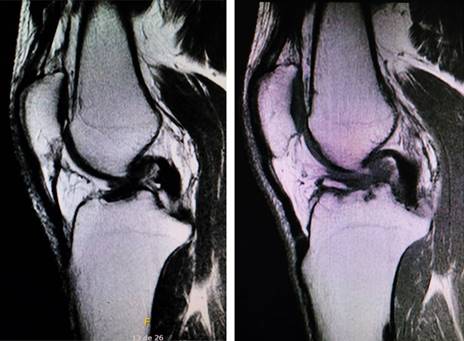

Nuestro paciente es un hombre de 40 años, quien sufrió una lesión del LCA derecho tres meses previos a la lesión de la rodilla izquierda. En ambas rodillas, se lesionó con mecanismos rotacionales en actividades no deportivas (Figura 1). Fue operado tres meses posteriores a la lesión de la rodilla izquierda (seis meses de evolución de la lesión de la rodilla derecha). La intervención se realizó sin torniquete, de manera simultánea, con dos equipos quirúrgicos y dos artroscopios. En ambos procedimientos se realizó inicialmente la toma de injerto autólogo de isquiotibiales y de manera subsecuente la artroscopía.

Figura 1: Resonancia magnética preoperatoria de ambas rodillas. En el lado izquierdo, observamos la imagen de la rodilla derecha. La rodilla izquierda se muestra en la imagen del lado derecho.